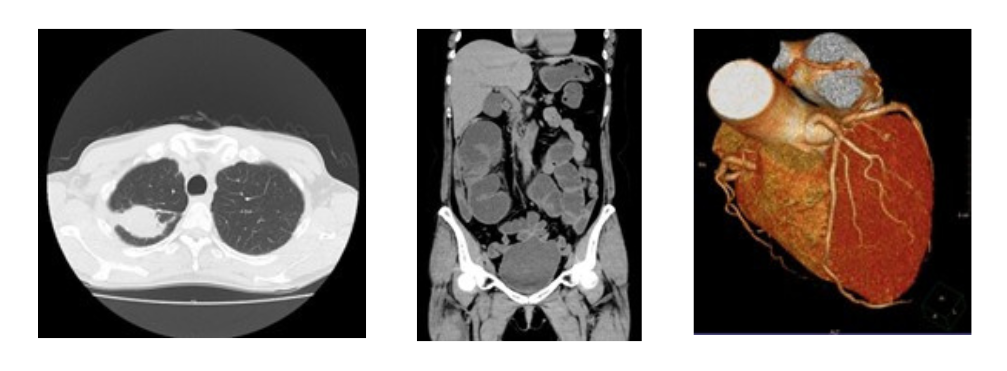

CTとはコンピューテッドトモグラフィーの略で、X線を用いて体の断面像(輪切り像)を撮影する検査です。

2025年3月31日よりキャノンメディカルシステムズ社製80列マルチスライスCTを使用しています。

マルチスライスCTでは頭部・胸部・腹部・下肢など全身の撮影ができます。3次元の情報により様々な断面の画像や3D画像を作成することができます。これにより病変の描出もしやすくなり、「がん」などの早期発見にもつながります。

AI技術を応用し、従来よりも低い線量で撮影を行っており、線量を下げてもより高画質な画像を得る事ができます。

胸部撮影の場合約4秒、胸腹部でも10秒程度息を止めるだけで高精細画像を得ることが出来ます。

【胸部】 【腹部】 【心臓】

心疾患は、「がん」に次いで日本人の死亡原因の第2位となっています。

とくに冠動脈の動脈硬化によって狭くなったり詰まったりして起こる狭心症や心筋梗塞が増加の傾向にあります。

心臓の栄養血管である冠状動脈の3次元画像表示により、以前は心臓カテーテル検査のため入院しなければ評価できなかった冠動脈が、外来診療において非侵襲的に評価することが可能となっています。

80列CTの特徴

検出器の列数は、体のまわりを検出器が一回転で撮影できる範囲と大きく関係し、列数が多いと同じ範囲をより細かく、より短時間で撮影することができます。胸部撮影の場合約4秒、胸腹部でも10秒程度息を止めるだけで高精細画像を得ることが出来ます。